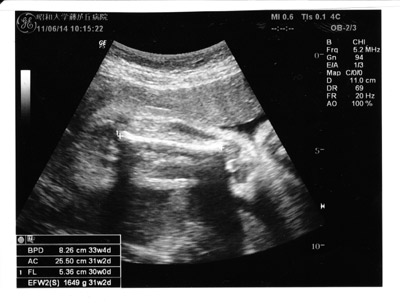

今日はおママの検診日だった。

胎児は順調、1,600gと少し大きめなのだそう。

逆子状態であるが、よく動くし経産婦なので、

生まれるまでには正常な向きになるのではないだろう、との事。

写真を撮ってもらえなかった。

最後にカルテから1枚剥がして頂いた。

それ用の写真ではないので、

何がドコなんだかさっぱり・・・。

時期については36週目の健診で見通しが出されるそうだ。

性別はまだわからなかった。